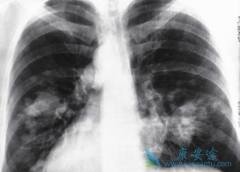

印度特罗凯 (GRLONAT)是一种口服给药的小分子EGFR TKI,已被批准用于NSCLC的一线治疗。EGFR是HER或Erb-B受体酪氨酸激酶家族的成员,已涉及癌症的发展和进展,并且在许多人类恶性肿瘤中表达,包括NSCLC。特罗凯(厄洛替尼)与EGFR受体的细胞内部分结合 ...